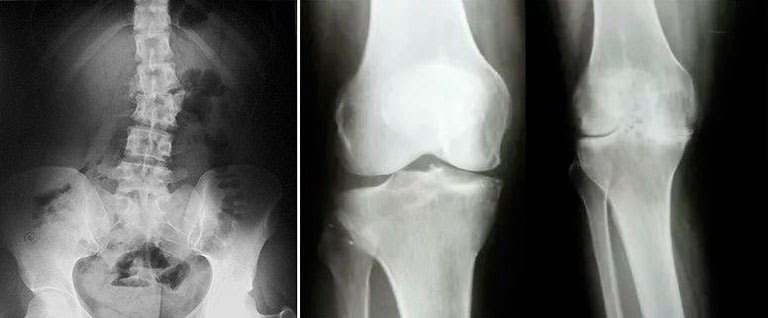

Obavili su kompletan pregled, uradili testove, slikali me , lekar (starija žena) mi je dijagnostikovala artritis, artrozu i osteohondrozu kičme, pokazala mi rendgenske snimke i rezultate opšteg pregleda. Odmah sam se setio svoje svekrve, jer je i ona imala dijagnozu pre 6 godina, a 6 godina se kretala u invalidskim kolicima, uplašio sam se! Što se tiče osteohondroze leđa u mojoj fazi, rekla je da ako se ništa ne preduzme, može zakrčiti živce u leđima, tako da delovi tela mogu početi da propadaju, pošto kod osteohondroze zglobovi se deformišu i mogu da vam stisnu živce, rekla je i ako ne lečim artritis i artrozu, onda takođe Mogu postati osoba sa invaliditetom bez nogu, ukratko, puni PPC, da budem iskrena, ne mogu preneti svoje stanje u tom trenutku, i što je najvažnije, sećam se kako je rekla: „Sa godinama, rizik od artritisa se samo povećava, pa prevenciju treba započeti od mladosti, šta je sa tim? nisam znao?" Da budem iskren, bio sam bez slike iz ove situacije! Pokušala me je nagovoriti na operaciju, kaže da nema drugog izlaza. Operacija je bila jako skupa, a osim toga, nisam mlad, hoću li se oporaviti nakon takve operacije, pomislio sam.

Pomislio sam: "Idem u bolnicu, šta će oni tamo reći." Odlučio sam da odem u bolnicu i fotografišem se kako bih bio siguran da je sve u redu. Doktor mi je rekao da postoji greška, nemate artrozu i artritis! Raširila je ruke i nije znala šta da kaže, osetio sam se jako neprijatno zbog pogrešne dijagnoze! A kao odgovor dajem joj svoje stare slike u ruke: „, I rekao pomogla mi je krema koju sam sa Interneta porucio Artropan ! Jeste li čuli za ovo? " Ona ćuti u odgovoru, sagnuvši glavu, nakon tri minute ćutanja agresivno odgovara: „Da, znam mnogo o Artropanu , delotvorna je , tako da se ljudi brzo oporavljaju nakon tretmsns ! ” Posle takvog odgovora, tiho sam otišao. Ispod ću napisati rezultate svojih istraga.